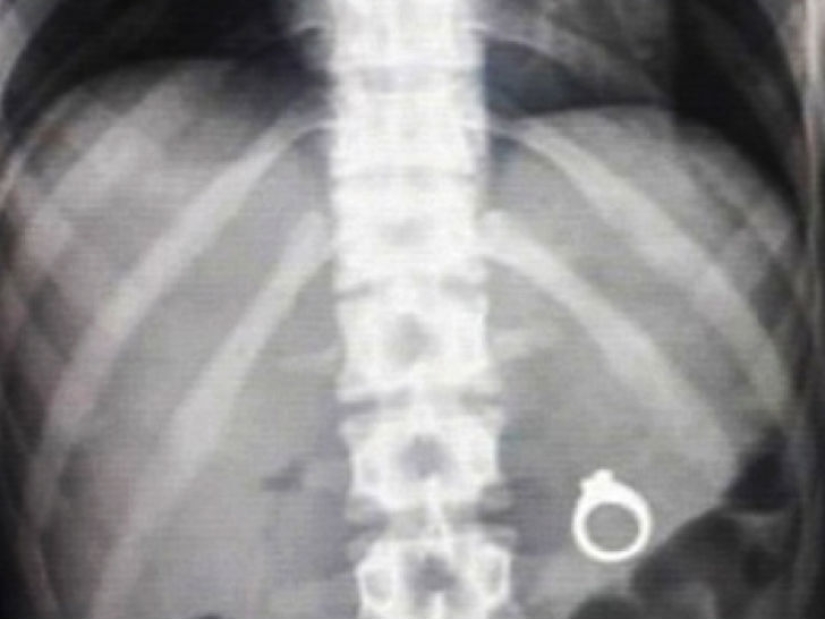

Muchos hombres quieren ser románticos y hacer una oferta a su mitad de alguna manera inusual. Y muchas personas utilizan, por ejemplo, la comida para ocultar una sorpresa en forma de un anillo allí. Así que, hombres, hagan una oferta antes de que su prometida decida probar este plato con una sorpresa.